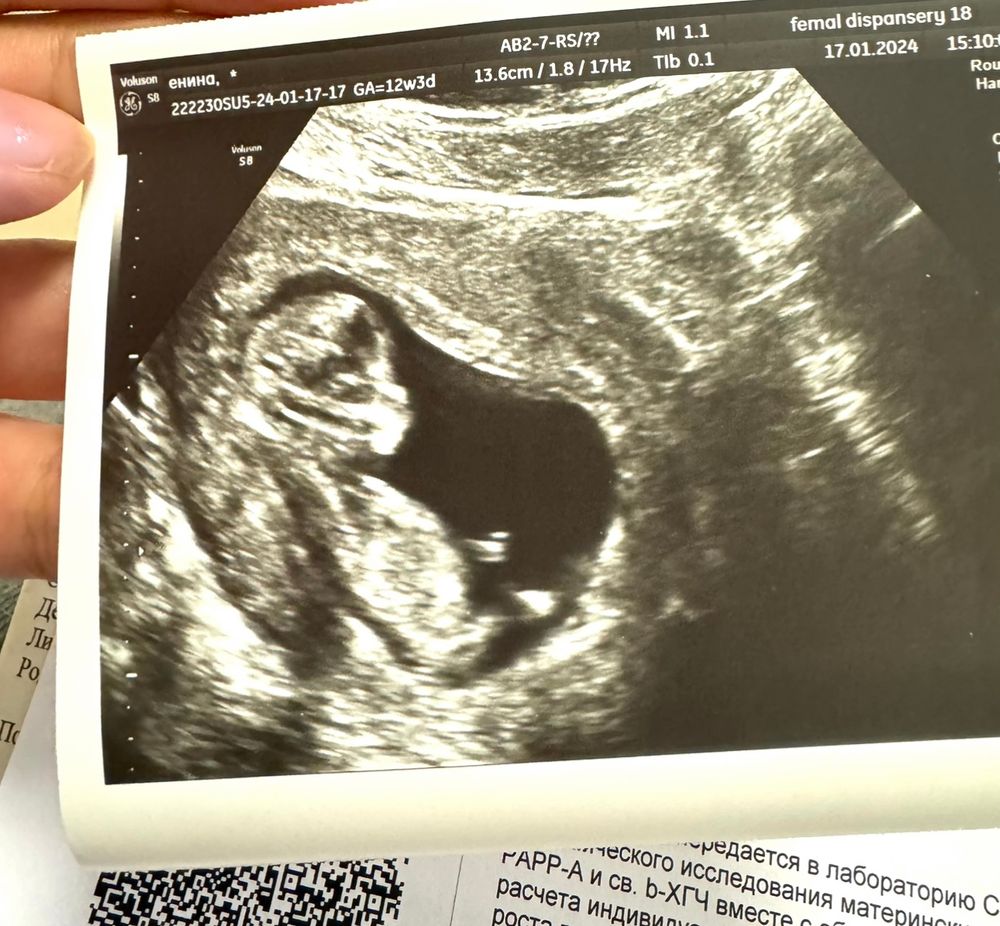

Определение пола в 14 недель, мальчик?

У меня так же по узи на скринах, то чётко мальчик, то девочка. Оказалась девочка и по узи и по крови в 10 недель, по второму скрину понятно, что у вас девочка скорее всего

Достовернее всего скажет анализ крови на определение пола. На вашем сроке уже информативен этот анализ будет. Узи дело такое… чаще всего верное конечно в наше время, но бывают исключения. Свекрови говорили, что будет девочка вплоть до родов, а родился мой муж))) Даже вещи все девчачьи были у него в младенчестве)))) Поэтому многое зависит от положения малыша, опытности узиста и аппарата узи Я лично сдавала кровь, не хотелось сюрпризов на поздних сроках или в родах